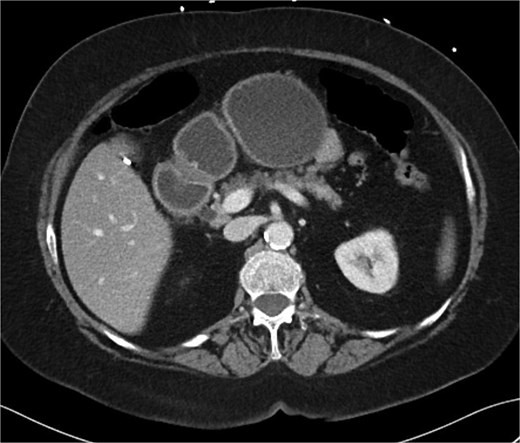

A 70-year-old woman with obesity, non-insulin-dependent diabetes, gastroesophageal reflux disease (GERD), cholecystectomy, and prior RYGB presented to the ED with acute chest and lower abdominal pain. The pain began 1 day earlier and initially responded to Ibuprofen, which she had been taking 4–6 times daily for musculoskeletal discomfort. Her pain worsened, radiating to her back, and was accompanied by belching and vomiting with dry heaving. She denied trauma or changes in bowel habits. Initial CT (Fig. 1) imaging showed a moderate hyperdense area around the duodenum, distension of the afferent limb and excluded stomach, and expected postoperative changes. She was admitted for conservative management. Four days later, a repeat CT (Fig. 2) was performed due to persistent symptoms, revealing free fluid in the intraperitoneal and retroperitoneal spaces, raising concern for duodenal perforation. She developed lethargy and diffuse abdominal tenderness and was taken to the operating room. Exploratory laparotomy with peritoneal washout, enterolysis, partial omentectomy was performed. It revealed two 1 cm posterolateral perforations of D3, which were repaired with an omental pedicle flap. The Roux limb was healthy, the jejunojejunostomy was dilated but patent, and the biliopancreatic limb was intact. Due to high vasopressor requirements, a temporary abdominal closure device was placed, and she was transferred to the surgical ICU. After stabilization, a second-look laparotomy was performed the next day to reinforce the duodenal closure, place a gastrostomy tube for drainage, and insert a J-tube for feeding (Figs 3 and 4). The abdominal wall was closed. On postoperative day 2, a CT with contrast showed extravasation from the duodenal repair site. Interventional radiology placed a transhepatic biliary drain to divert bile and support duodenal patch healing. Helicobacter pylori antigen was negative. Her condition improved, and she was started on an enteral and slow oral feeding regimen. However, at this juncture, the patient declined further treatment and requested comfort care measures.

Intra-operative image showing pyloroplasty and omental patch repair.